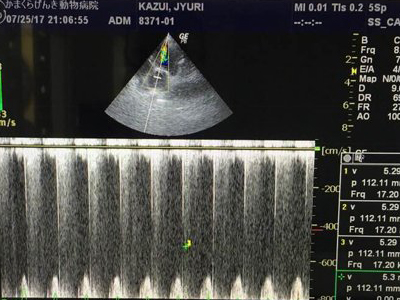

エコー検査は超音波を用いて心臓を視覚的にイメージするものです。

この安全かつ簡便な方法によって、心臓の構造や機能に関する情報を得ることができます。